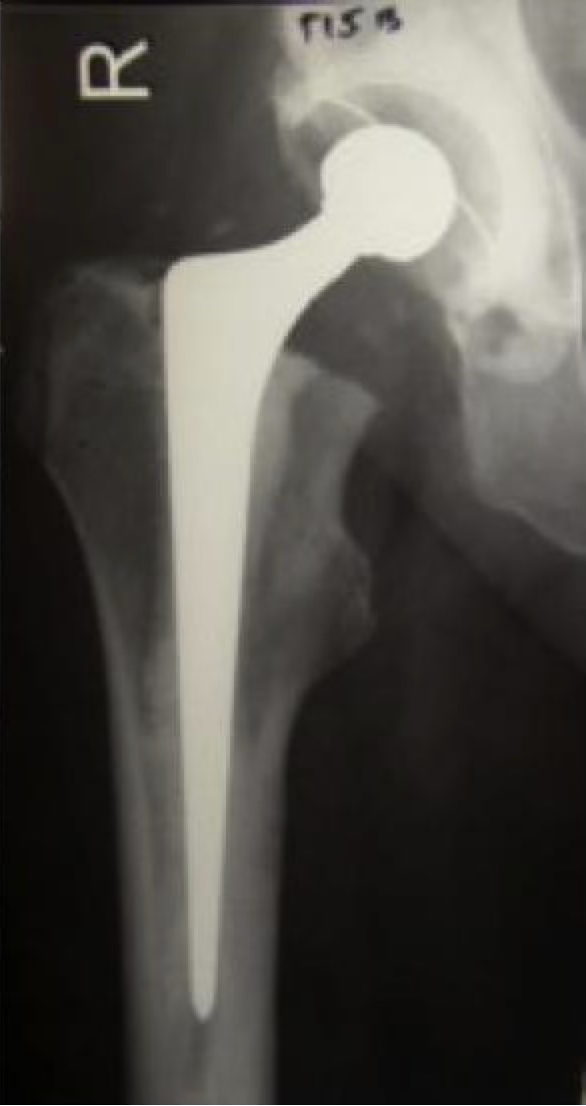

Primary THA

Implant Fixation & Bearing Surface

• Most common construct: Cemented MoP, 4.87% revision in 14 years

• 75 years: All bearing surface combinations (except MoM) perform similarly

• <55 years: CoP shows better results (<4%) compared to MoP (8-10%)

THA of Choice

• Cemented Exeter Hip: Long-term performance, ODEP rating A* at 10 years

• Ceramic Femoral Head with 1st or 2nd gen XLPE

• <55 years: Discuss uncemented THA option

Cemented THA

• Immediate solid fixation

• Proven, durable

• Low failure rate

• Meets NICE guidelines

• Cheaper, easier to revise